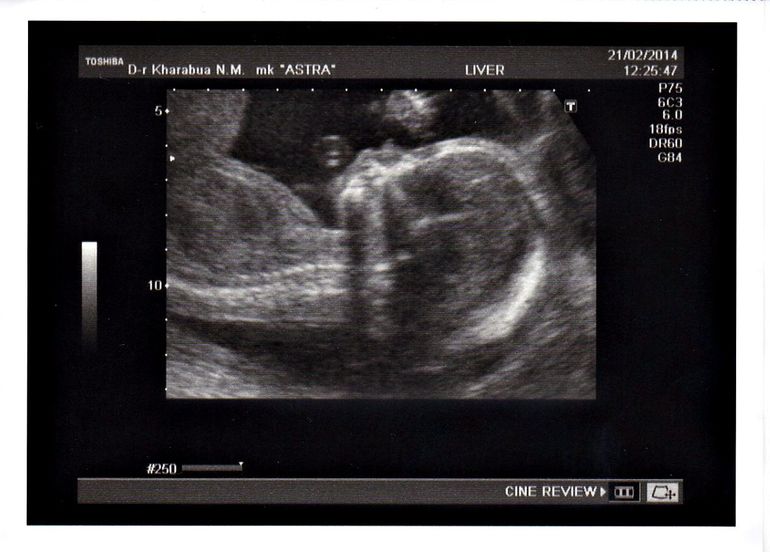

2е плановое узи))

Были вчера на узи)))Все у нас в порядке, лялечка здорова))Срок, как и на предыдущем узи, на неделю меньше чем по м,сейчас у нас 20 недель))Лежит

поперек, но эт не страшно, перевернется еще))Весит уже целых 345

грамм)))И главное, нам подтвердили таки девочку

))Будет у нашей Лизули

сестренка Варвара))Самое интересное что муж не сомневался вообще, сразу,

как только забеременела, сказал что девочка будет))